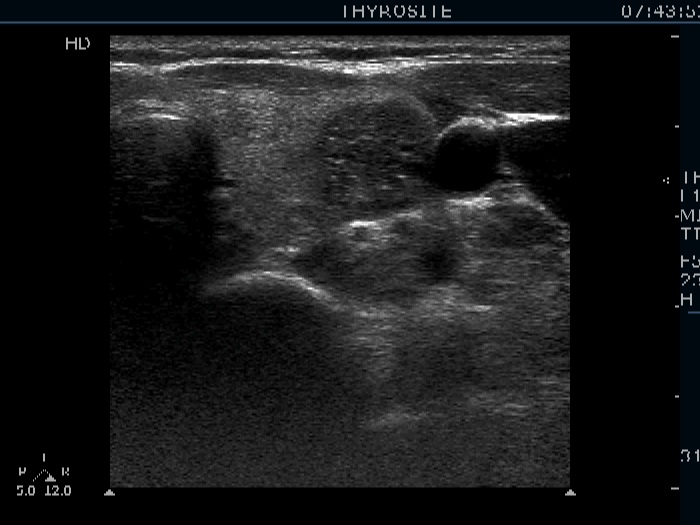

First examination (first row of images):

Clinical presentation: A 57-year-old woman was referred for aspiration cytology of a multinodular goiter has been known for more than two decades. The patient had no complaints.

Functional state: euthyroidism with TSH 0.96 mIU/L.

Ultrasonography. The thyroid was echonormal and was composed of multiple nodules. Most of them were hyperechogenic or minimally hypoechogenic. There was a hypoechogenic nodule presenting bright hyperechogenic granules in the upper part of the left lobe.

Cytology resulted in benign colloid goiter.